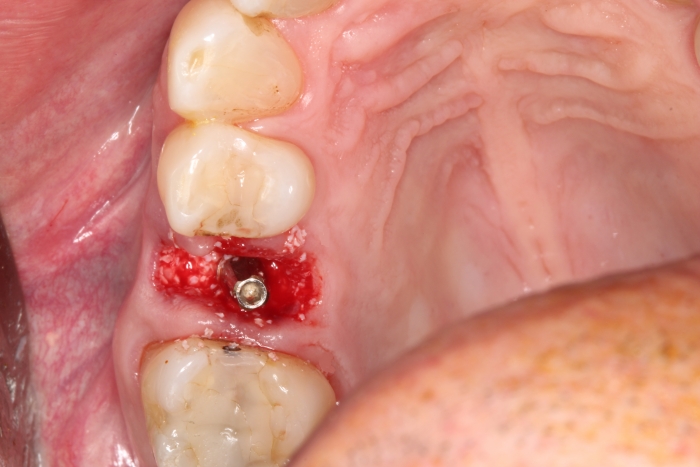

Extração - Implante imediato

Implante - Enxerto ósseo sintético